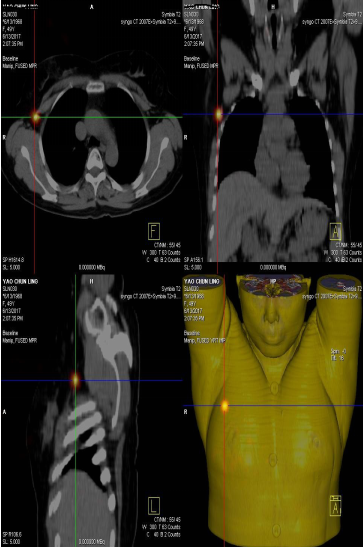

前哨淋巴結(jié)顯像技術(shù)一般在腫瘤附近注射放射性核素標(biāo)記特殊藥物,這種藥物會(huì)被前哨淋巴結(jié)攝取,存在于前哨淋巴結(jié)中。24小時(shí)之內(nèi)都可用SPECT-CT進(jìn)行前哨淋巴結(jié)顯像檢查。

患者李女士,發(fā)現(xiàn)右側(cè)乳腺腫物,來(lái)我院就診,行乳腺腫物局部擴(kuò)大切除術(shù),術(shù)后病理回報(bào):右乳腺浸潤(rùn)性導(dǎo)管癌III級(jí),伴原位癌。擬行右乳腺癌切除術(shù),提檢前哨淋巴結(jié)顯像檢查,明確有無(wú)淋巴結(jié)轉(zhuǎn)移。